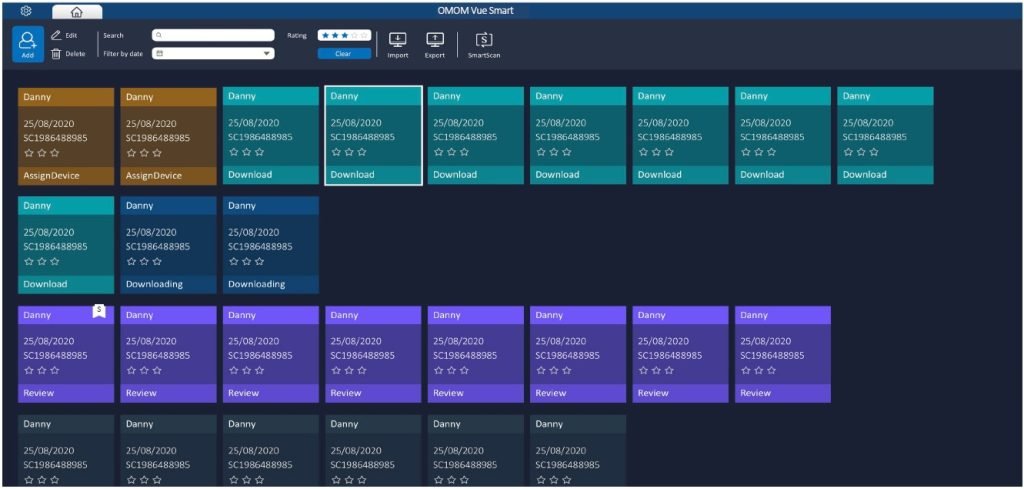

VueSmart čitanje ne može biti lakše

Uz veliku nadogradnju centra za upravljanje pacijentima i ekrana za čitanje, novi Vue Smart softver pruža zdravstvenim radnicima još jednostavniji interfejs i iskustvo čitanja bez stresa.

Sa našim naprednim AI algoritmima, Vue Smart je na novoj tehnološkoj granici u funkcionalnosti brisanja, otkrivanje lezija i klasifikacija koja garantuje lakšu nego ikada interpretaciju kao i poboljšani klinički ishodi.

Koristeći naše algoritme, SmartScan obrađuje neobrađene datoteke brisanjem do 90% snimka, identifikujući i označavajući čak 16 vrsta abnormalnosti. Nakon Smartscaning-a, SmartView i SmartFinding su spremni za upotrebu.

Režim čitanja SmartView će reprodukovati samo slike koje je pokupio Smartscan, pomažući korisnicima u tome brzo kretanje kroz ceo video. Istaknute oznake iznad vremenske trake prikazuju slike koji se može prikazati kao kratak video.

Snimanjem najistaknutijih karakteristika odabranih slika sa prediktivnim rezultatima, SmartFinding pomaže lekarima tako što prikazuje abnormalnosti i predlaže opise. Slike se prikazuju kao prikaz stranice.